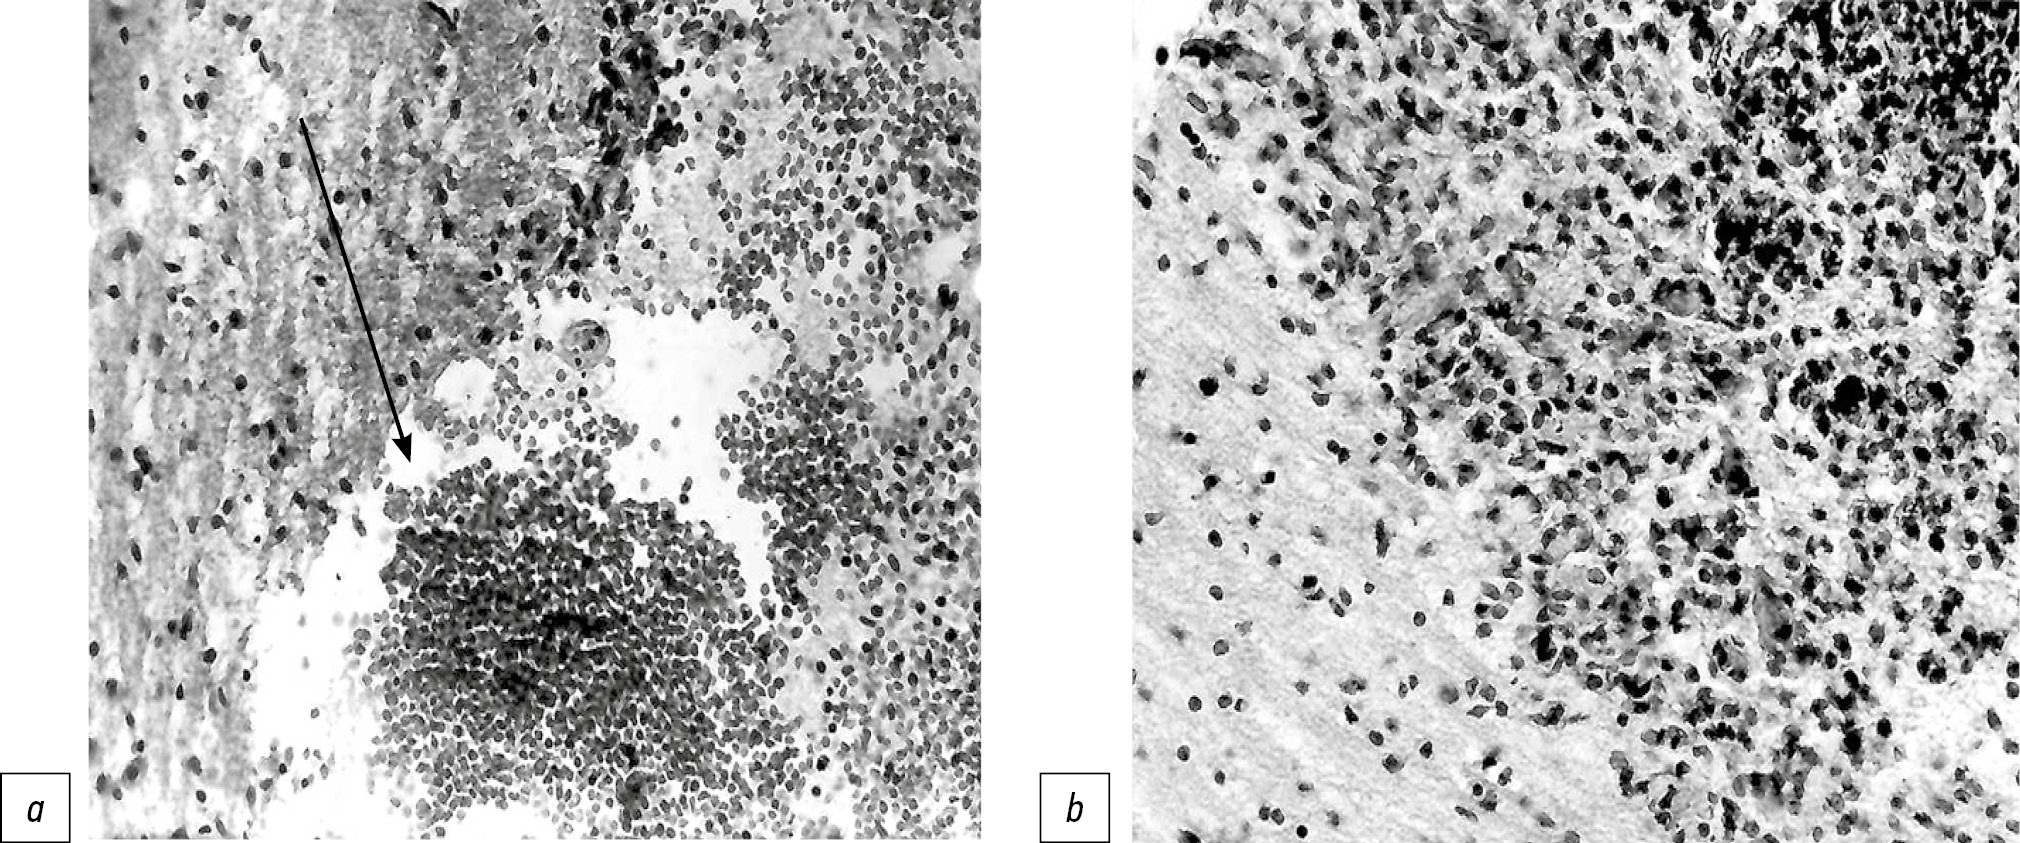

В печени после нанесения травмы сформировалась зона некроза, представленная розовой аморфной массой с примесью эритроцитов, в которой определялись гепатоциты с размытыми границами с признаками кариолизиса. Площадь повреждения составляла 3085,7±368,3 мкм2. С 1-х суток после операции в печени нарастало число митозов гепатоцитов (4,5±1,4; в контроле — 1,5±0,7). Активация митотической активности гепатоцитов подтверждалась повышенным количеством у опытных плодов Ki-67-позитивных ядер в гепатоцитах по сравнению с контрольными животными (15,3±0,7 на 7-е сутки; в контроле — 6,4±0,8) (рис. 4). Пик митозов наблюдался в сроки от 2 до 7 сут (8,0±3,5 — на 7-е сутки; в контроле — 3,6±0,7). Начиная с 7-х суток по мере снижения числа митозов увеличивалось число двуядерных гепатоцитов (38,1±5,2 — на 7-е сутки; в контроле — 25,3±4,5), что продолжалось до конца эксперимента (37,1±4,6 — на 30-е сутки; в контроле — 26,4±3,6).

Рис. 4. Позитивная реакция ядерного белка Кi-67 в ядрах гепатоцитов, 7-е сутки после операции: а — контрольное животное; b — опытное животное. Иммунногистохимическое окрашивание, ×400.

Fig. 4. Positive reaction of the nuclear protein Ki-67 in nuclears of hepatocytes, 7th day after the operation: а — control animal; b — experienced animal. Immunohistochemical staining, ×400.